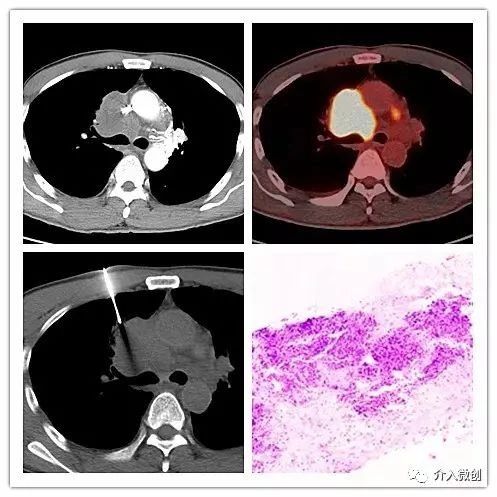

例1:肺小细胞神经内分泌癌(NEC)伴上腔静脉综合征

- 老年男性,胸闷、气促、咳嗽1月余。

- 增强CT示右前上纵隔肿物,侵犯压迫上腔静脉;PET-CT显示右前上纵隔高代谢病灶。

- CT引导下肿物穿刺活检病理显示:小细胞神经内分泌癌(Ki-67约80%),考虑肺来源。

CT引导下穿刺活检